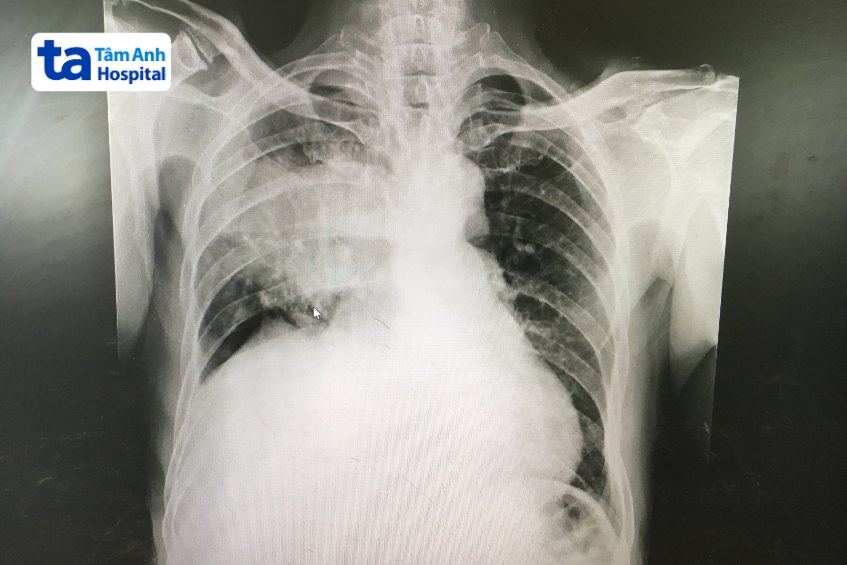

Cơ chế hoạt động như sau: Vi sinh vật xâm nhập vào phổi và bắt đầu nhân lên, từ đó giải phóng độc tố gây viêm, phù nề nhu mô phổi, dẫn đến đông đặc hoặc đông cứng tế bào phổi. Tình trạng này có thể quan sát thấy thông qua kết quả chụp X-quang.

Để chẩn đoán viêm phổi thùy, bác sĩ có thể chỉ định thực hiện các xét nghiệm chẩn đoán hình ảnh sau: (3)

Đối với viêm phổi thùy, khuyến cáo cần theo dõi bằng X-quang ngực/ CT trung bình sau 11,5 tuần điều trị để tầm soát, theo dõi, chẩn đoán sớm các bệnh lý phổi ác tính hoặc lành tính.